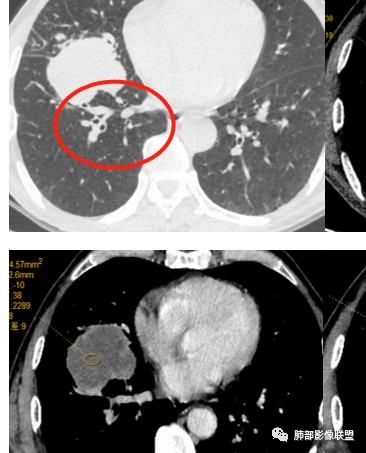

右肺巨大肿块,跨叶生长,其内见大片状坏死,坏死边界不清,血管进入,边缘受侵,病灶边缘可见毛刺及分叶,病灶强化方式速升速降,纵隔内见坏死强化淋巴结,周围肺叶小叶间隔结节样增厚,考虑恶性腺癌并淋巴结转移及癌性淋巴管炎,鉴别肉瘤。

右肺中叶可见类圆形软组织密度肿块影,右肺中叶外侧段支气管狭窄截断。肿块密度不均,边缘毛燥不规则,可见毛刺。远侧肺内可见网格条索影。增强后可见不均匀强化。纵隔淋巴结肿大,部分融合。考虑右肺恶性病变,鳞癌>腺癌,并纵隔淋巴结转移。

患者中老年男性,体检发现肺部占位。

胸CT:右肺中叶实性占位性病变,呈膨胀性生长,对斜裂明显挤压,右肺中叶外侧段阻塞,并在边缘可见分叶、毛刺、棘突样改变,胸膜牵拉;增强可见病灶明显强化,可见边缘模糊血管影,病灶内可见大片状低密度区,隆突下可见肿大淋巴结。

诊断考虑:恶性病变。

右肺巨大肿块,横跨上中下三叶,主体在中叶,外侧段近端支气管截断,膨隆分叶,毛刺,网格,淋巴结大,不均匀强化,湖泊样坏死,考虑恶性,低分化鳞癌>腺

右肺肿块,横跨上中下三叶,主体在中叶,外侧段近端支气管截断,膨隆分叶,毛刺,网格,淋巴结大,不均匀强化,有坏死,鳞癌?

老年男性,查体发现,右肺上叶中叶巨大肿块,有分叶,周围有条索影,支气管受压推移,内有大片及小灶坏死,坏死边界有的清楚有的不清,周围明显强化,纵隔有肿大淋巴结,跨叶生长,考虑恶性,腺癌或肉瘤样癌

右肺中叶可见类圆形软组织密度肿块影,支气管狭窄截断。肿块密度不均,边缘毛燥不规则,可见毛刺。增强后可见不均匀强化。纵隔淋巴结肿大,部分融合。考虑右肺恶性病变,鳞癌?

老年男性,右肺上叶可见一团块影,边界清,有膨隆,有凹陷,棘突,有分叶,密度不均匀,周边可见癌性淋巴管炎,跨叶裂,支气管阻塞?受压?狭窄,纵隔淋巴结肿大,考虑恶性,腺癌可能

右肺跨上叶与中叶一实性肿块影,中叶外侧段支气管堵塞,肿块有明显分叶、毛刺、棘突样改变,胸膜牵拉,周围有小花小草;增强可见病灶明显强化,病灶内可见大片状低密度区,以外侧为主,隆突下可见肿大淋巴结,恶性,考虑鳞癌可能。

老年人,右肺上叶软组织肿块,边界清晰,有浅分叶,右肺上叶支气管受阻,增强后病灶边缘强化,内部似有延迟强化,内见血管造影征,其血管边缘毛糙,纵隔可见增大淋巴结,考虑恶性肿瘤,无明显阻塞性肺炎和不张,考虑腺癌或腺鳞癌伴纵隔淋巴结转移

老年男性,体检发现右肺巨大肿块,右肺跨叶生长,可见支气管截断,边缘见分叶,毛刺,右肺支气管不通,增强后边缘强化,内部示大片低密度坏死区,边界不清,周围肺组织小叶间隔增厚,纵隔见多发肿大淋巴结。考虑为恶性并淋巴结转移。

右肺肺门肿块,自肺门向外延伸,外大内小,肿块呈长条状,平行支气管,近段支气管不规则堵塞,支气管无扩张壁无增厚,平扫密度均匀,增强后可见不规则坏死,病灶跨叶裂生长,纵隔淋巴结肿大,中老年男性,体检发现,无症状,考虑:恶性鳞癌,鉴别结核

老年男性,右肺跨裂生长团块灶,边缘浅分叶,内不均匀强化,无强化坏死区较多,可见支气管截断,周围阻塞性炎症,考虑恶性肿瘤可能,慢性肺脓肿待排

老年男性,右肺不规则跨叶肿块,有分叶,相邻支气管阻断,强化不均有低密度坏死区,坏死区边界较清,类似湖泊样,内见血管穿行,造影征,病灶远端可能有阻塞性炎症,总体考虑鳞癌。

患者中老年男性,体检发现右肺占位。血常规轻度贫血,AFP、CEA正常,肝肾功能、血糖、血脂、心肌酶、电解质正常。胸部CT:右肺中叶巨大肿块灶,垮叶生长,可见分叶、毛刺、血管集束、支气管截断征象,远端周围可见小叶间隔增厚,增强轻度强化,内可见低密度坏死区,综合淋巴结肿大,且可见淋巴结内似低密度灶。综合考虑恶性,鳞癌并癌性淋巴管炎可能大。鉴别结核、腺癌。

胸CT:右肺中叶团块样实性占位,边缘膨隆,中叶外侧段阻塞,病灶可见深分叶、棘突,胸膜牵拉;增强不均匀强化,可见边缘模糊血管影,病灶内大片状低密度区,纵隔多发肿大淋巴结。

诊断考虑:恶性病变,鳞?大细胞?鉴别:TB

右肺中叶巨大肿块,外侧段近端支气管截断,横跨上中下三叶,主体在中叶,膨隆分叶,毛刺,网格,淋巴结大,不均匀强化,伴阻塞性肺炎及肺不张,湖泊样坏死,考虑恶性,鳞癌可能性较大

右肺上叶肿块,跨叶生长,分叶,支气管截断,周围支气管受压推移,内有大片坏死,周围小叶间隔增厚,纵隔淋巴结肿大,明显强化,考虑肉瘤样癌。鉴别腺鳞癌。

病灶主体位于右肺中叶,跨上、下叶,分叶毛刺,外侧段支气管堵塞,大片坏死,边界不清,内见血管进入,增强快进快出,纵隔淋巴结肿大,小叶间隔增厚,恶性,腺癌或肉瘤样癌可能。

右肺门旁肿块,形态不规则,跨叶生长,近段支气管不规则堵塞,支气管局部增厚,密度欠均匀,增强后可见不规则坏死,纵隔淋巴结肿大,中老年男性,体检发现,考虑:恶性鳞癌